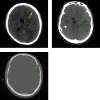

We report the case of 22-year-old man with nontraumatic intracystic hemorrhage into a middle cranial fossa arachnoid cyst associated with a contiguous subacute subdural hematoma. Arachnoid cysts are benign intra-arachnoidal fluid collections frequently detected incidentally during neuroimaging. Rare complications of arachnoid cysts such as intracystic hemorrhage or subdural hematomas and subdural hygromas typically occur after head trauma. Our review of the literature identified fewer than 30 cases of arachnoid cysts with complicating intracystic hemorrhage and ipsilateral subdural hematomas.